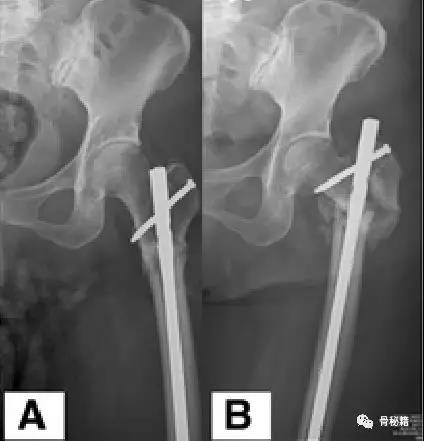

一个双膦酸盐治疗5年的患者粗隆下非典型骨折

采用了髓内钉固定,术后一年内固定失效